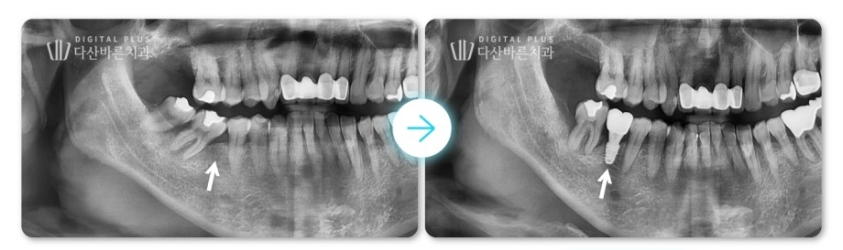

1. 인접치 이동 케이스

해당 환자분은 오른쪽 아래 어금니를 빠진 채로 방치하셔서

옆 인접 치아들이 빠진 치아 쪽으로 많이 기울어진 상태였는데요.

아래 파노라마 사진을 보면 치아가 기울어진 모습이 명확하게 확인됩니다.

▲ 초진 시 파노라마 사진. 빠진 치아 자리로 인접치들이 기울어진 모습.

▲ 교정치료 시작 5개월 후 치아 배열이 정돈되고, 임플란트 심을 자리가 형성된 모습.

보통 연세가 있을수록 뼈가 딱딱하게 굳기 때문에 교정 시 치아 이동 속도가 느린데,

우리 환자분은 50대 연세에도 불구하고, 5개월 만에 임플란트 심을 수 있는 공간이 형성되었습니다.

그럼 그 형성된 공간에 임플란트를 심으면 치료가 완성됩니다.

▲ 교정으로 형성된 공간에 임플란트 식립 후 무너진 치아 배열과 교합을 회복한 모습.

자연치아의 불필요한 발치 없이, 교정을 통해

치아를 이동시켜 임플란트를 심어준 케이스입니다.

이렇게 치료해 주면, 무너졌던 교합이 다시 정상으로 회복되어

음식 씹기도 편하고, 치아 사이 음식물이 끼는 일도 줄어들게 됩니다.

<최종 치료 전후 사진>